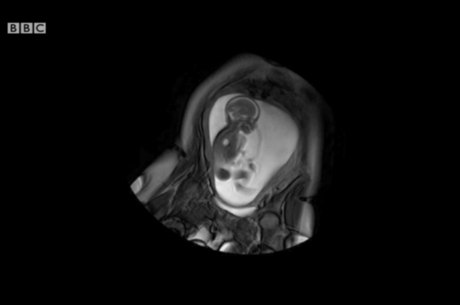

Cientistas fazem mapa do cérebro de bebês

Cientistas querem mapear cérebro de bebê ainda no útero

Reprodução / BBC

Estudo envolve período imediatamente antes e depois do nascimento e pode ajudar a prevenir doenças

Cientistas britânicos deram início a um projeto de seis anos para mapear as conexões nervosas desenvolvidas no cérebro de um bebê ainda no útero e imediatamente após o nascimento.